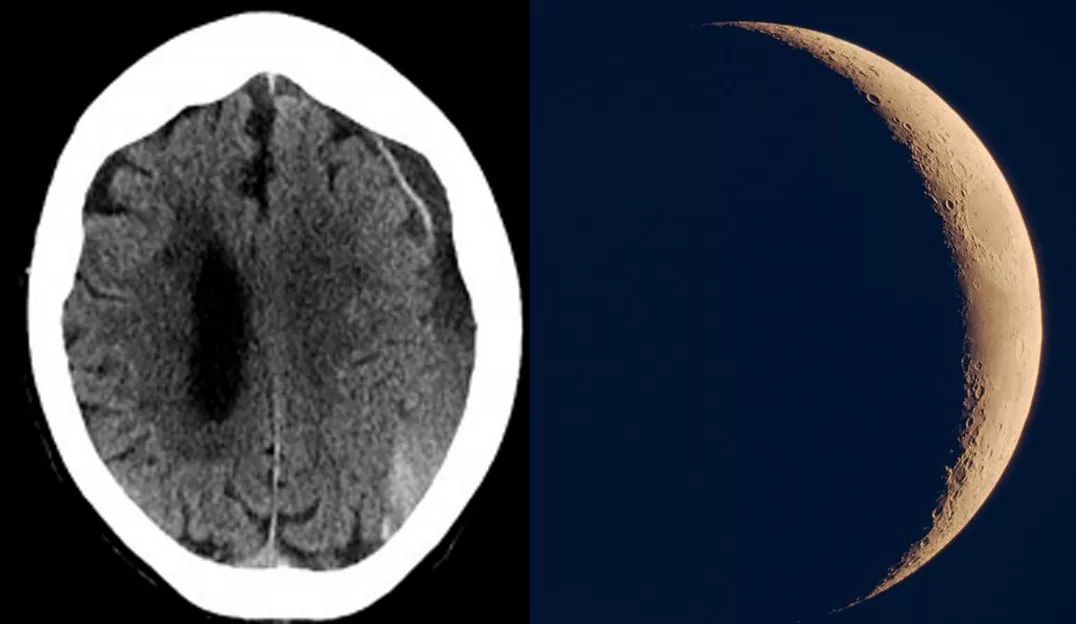

脑部影像出现“新月”形态,基本可确诊为CSDH

慢性硬膜下血肿,都是月亮惹的祸? 中秋刚过,月亮也开始慢慢地改变它的形态。慢性硬膜下血肿的形态非常有特征性,其形态如新月,见到脑内出现“新月”,基本上确定为本病无疑。

新月如钩

其发现多因逐渐加重出现的症状,如头痛、呕吐、淡漠、偏瘫、麻木、失语、记忆力下降、定向力障碍和智力迟钝等 ,追诉病史3周前多有外伤史。行CT扫描发现呈新月形或半月形高密度或等密度影。